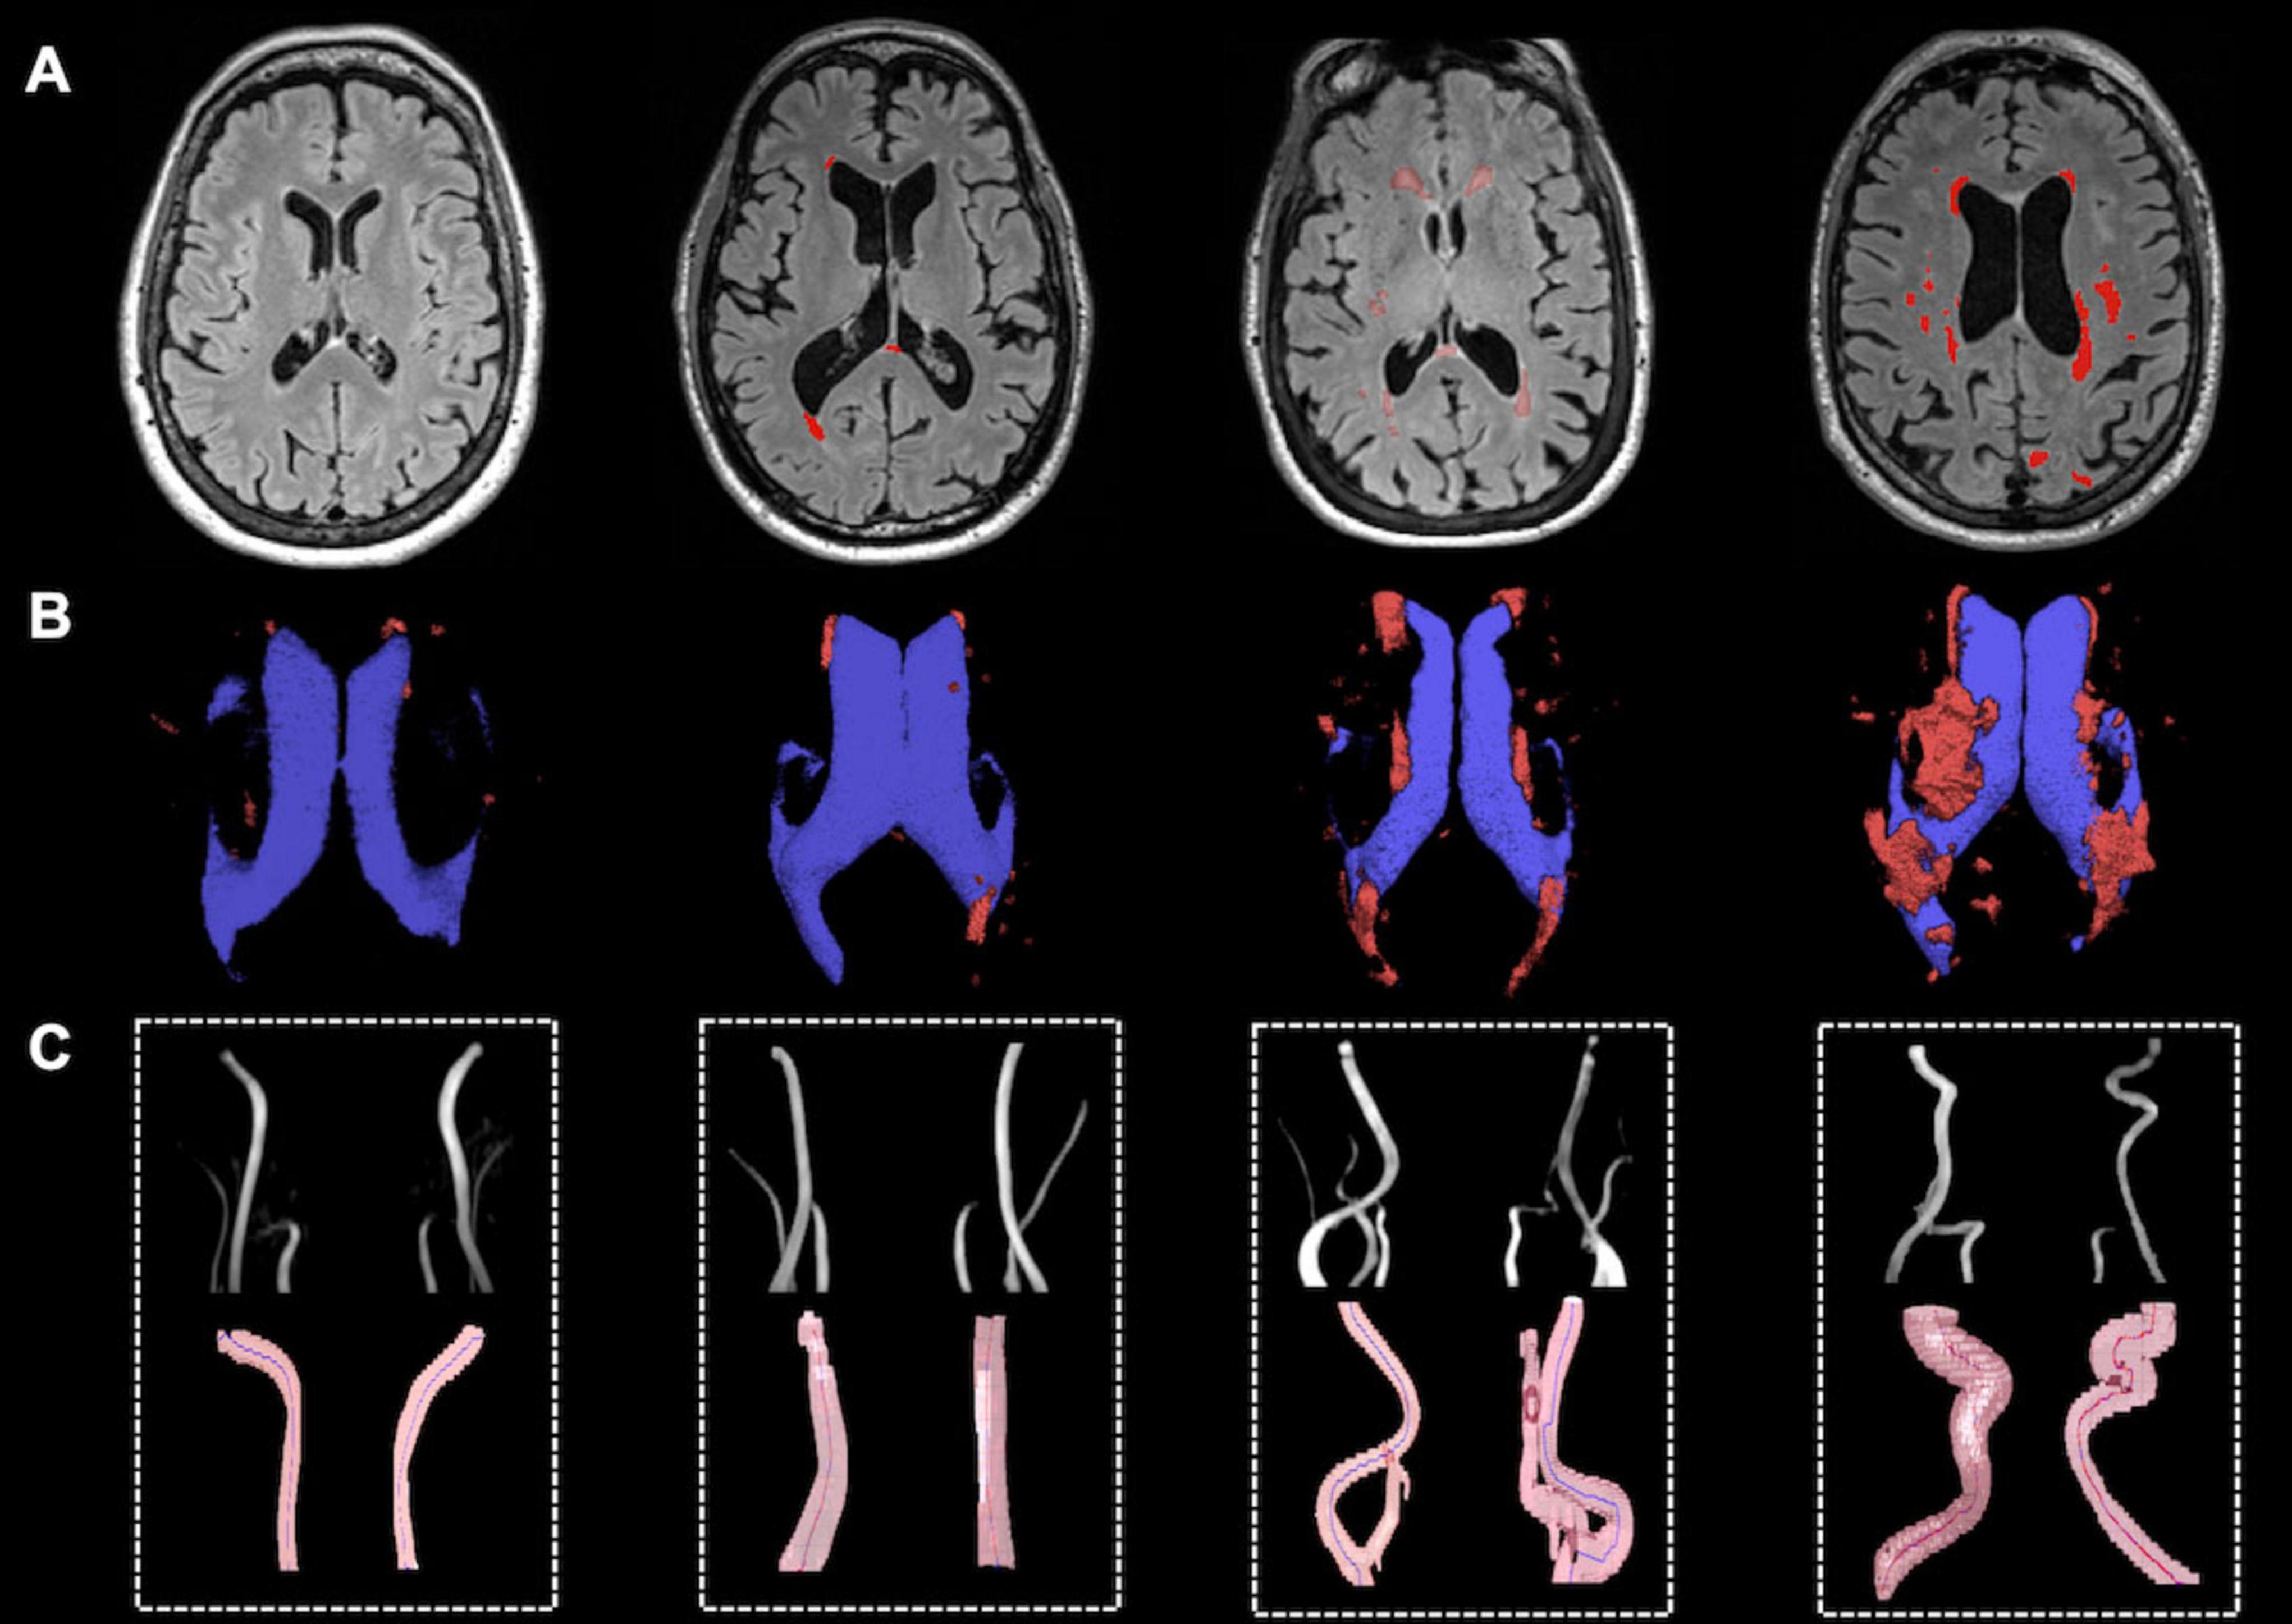

Qualitative analysis indicated that subjects with more tortuous neck brain-feeding arteries tended to exhibit a higher WML load (Figure 4). Multiple linear regression was further conducted to examine the relationship between tortuosity metrics and lesion volumes across different WML categories. The regression model for total WML volume explained 30.6% of the variance (r2 = 0.31, adjusted r2 = 0.22; F(7, 56) = 3.53, p = 0.003). For PVWMLs, the regression model explained 32.7% of the variance (r2 = 0.33, adjusted r2 = 0.24; F(7, 56) = 3.88, p = 0.002). In contrast, the model for DWMLs did not reach statistical significance (r2 = 0.20, adjusted r2 = 0.10, F(7, 56) = 2.03, p = 0.07). Table 3 summarizes the regression coefficients (β) and their significance levels for each lesion category.

Figure 4. Representative illustration of WMH lesions and tortuous ICAs and VAs. (A) WMH lesion on FLAIR MRI; (B) Lateral ventricle (blue) and WM lesion segmentations (red); (C) Vascular segmentation and centerline tracking showed subjects with higher lesion load had higher tortuosity level.

Specifically, the ICMindex showed a significant positive association with total WML volume (β = 1.204; 95% CI: 0.319–2.090; p = 0.009) and PVWMLs (β = 1.504; 95% CI: 0.337–1.770, p = 0.005) (Figures 5A, B). However, ICMindex was not significantly associated with DWMLs (p = 0.34). Additionally, ICA angle was not significantly related to lesion volumes in any category (total WMLs: p = 0.42; PVWMLs: p = 0.45; DWMLs: p = 0.49).